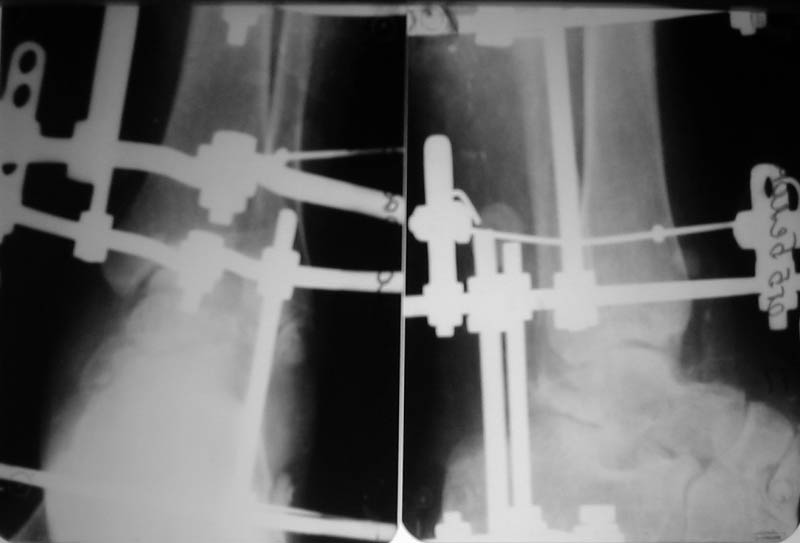

Диагноз: закрытый переломо-вывих таранной кости, двухлодыжечный перелом, подтаранный вывих стопы, асептические некрозы. Перелом был закрытый, но были некрозы из-за давления отломков (см.фото).

Что сделали. Под наркозом попытка закрытой ручной репозиции - безуспешно. Латеральный доступ, открытая репозиция таранной кости. Наложение АВФ (2 кольца, 2 полукольца на пятке и переднем отделе стопы). Устранение подтаранного вывиха стопы. Послеоперационные снимки в приложении.